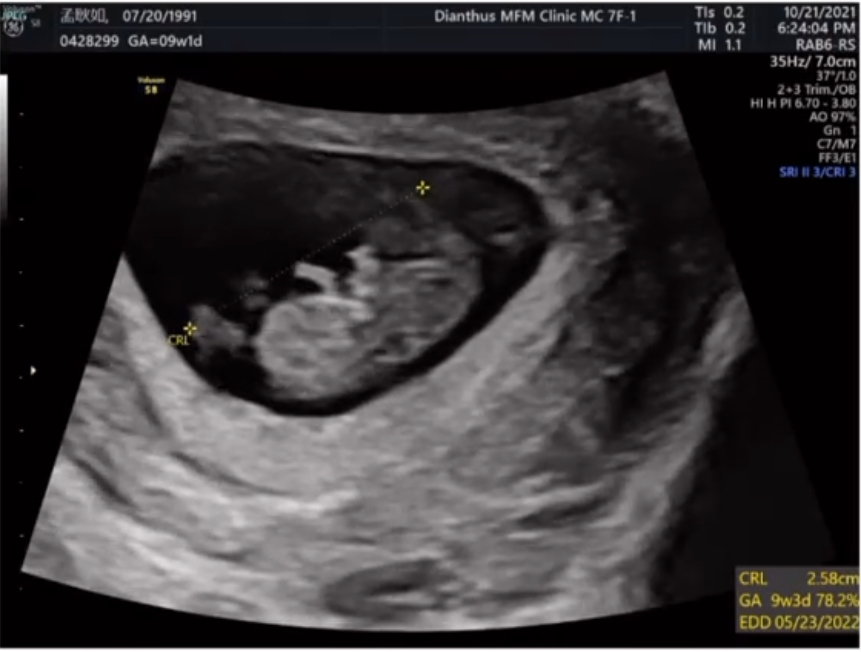

孟耿如在面子书上晒出超音波照,文字充满喜悦:“终于~~~可以开心的跟大家分享这个消息,目前不知道是小黄瓜还是黄玉米已经在肚子里3个月了,上面的超音波影片,是2个月的时候,他的小手手在跟我们打招呼”。